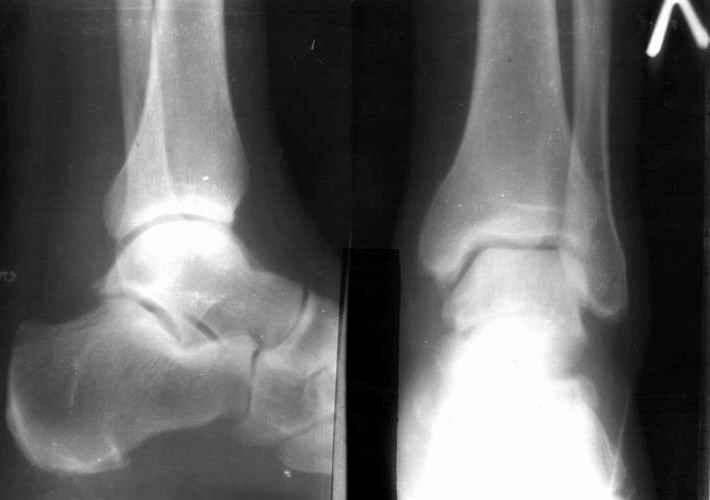

братился мужчина, 50 лет. Жалобы на боли в голеностопном суставе, периодическое подворачивание стопы вовнутрь. Получил травму 5 лет назад. При осмотре - признаки латеральной нестабильности, боли по ходу малоберцово-таранной, задней малоберцово-пяточной связки. Сделал стандартный Rg, и Rg с нагрузкой. В течение последнего года начали беспокоить боли в коленном, тазобедренном суставе. Как полагаю, это связано с нарушением биомеханики всей ноги. Если прооперировать и устранть нестабильность, пройдут ли эти боли (этот вопрос пациент задал сразу, как только услышал слово операция)? С ув. Сергей Мелашенко, Приморск, Запорожская обл. Ukraine

Попробуйте сделать аналогичный стресс -снимок прямой проекции здорового сустава и сравнив его с ранее травмированной стороной определитесь есть

нестабильность или нет.

С практической т.зр. удобно делать стресс -проекции одновременно двух суставов на одной кассете, супинируя обе стопы вместе и тогда разница ширины суставной щели даст вам информацию о стабильности или нестабильности сустава.

присоединяюсь к мнению показать симметричные снимки

пока не кажется, что нестабильность очевидна.